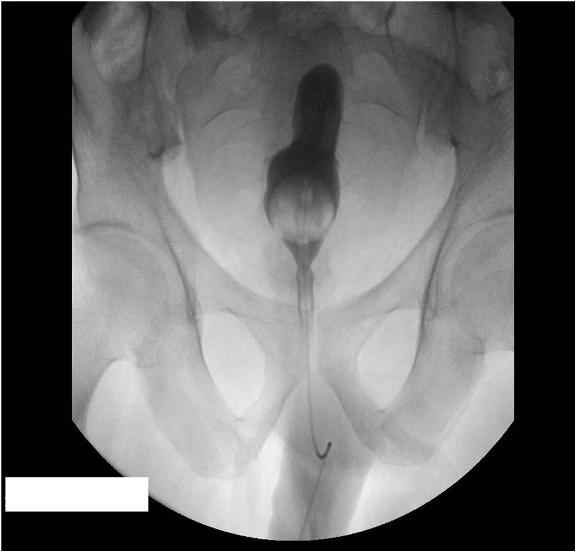

Pelvic Lipomatosis

Author(s)Sikander Ali Khan, MD